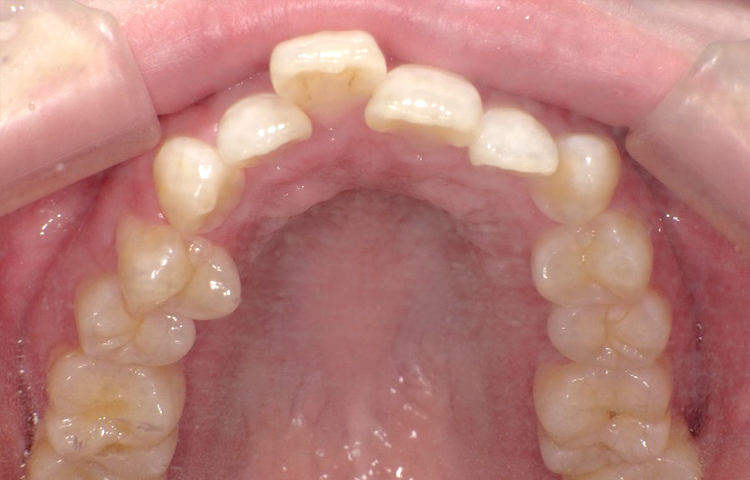

症例4

治療前

治療後

| 主訴 | 右上1番出ている 上のみ部分矯正希望 |

|---|---|

| 治療 期間 |

約8ヶ月 |

| 治療費 | 220,000円(税込)/調整費用別途 |

| 治療 内容 |

上の前歯部にワイヤーを着けて進めていく、プチ矯正で施術。 |

| 治療の リスク |

奥歯を動かさないので、前に出して並べていく。 歯と歯が移動するスペースを作るので、知覚過敏の症状がまれにでる。 装置による清掃の難しさから、歯肉炎や歯周病、虫歯の進行がするリスクが高まる。 歯を動かすことで、歯茎が下がるリスクある。 矯正終了後は、リテーナーを使用し、後戻りを防ぐ必要がある。 |